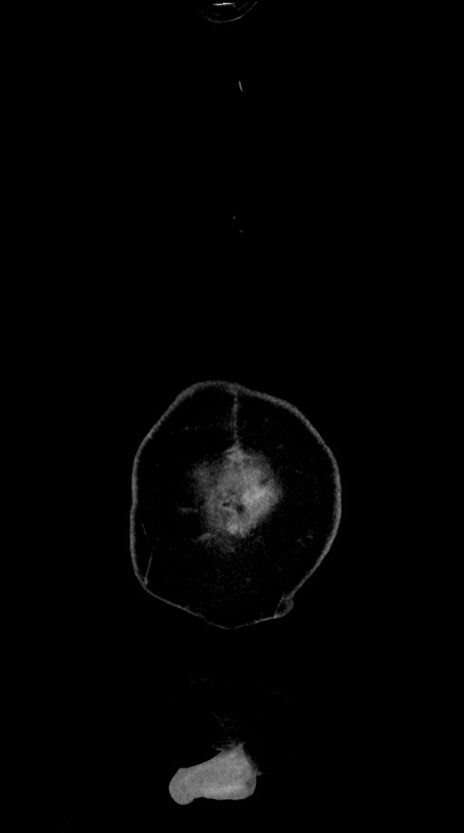

横断像